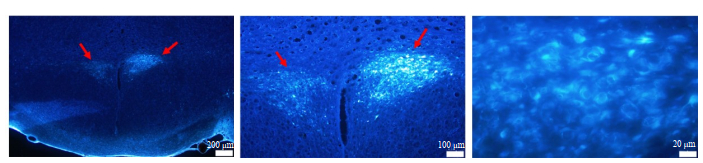

To investigate whether NAc neurons directly project to the RVLM, the retrograde tracer, FluoroGold, was injected into the RVLM. At 1 week after tracer injection, coronal sections of the brain (50 μm) were prepared for observation of FG labeling. Fluorescent analysis of these sections revealed the presence of retrogradely filled neurons in the NAc of both normal rats and AN model rats (Fig. 2), confirming the projection from NAc to the RVLM.

Fig.2 Fluorescent microscopic images of the neurons in the NAc labeled with FluoroGold injected in the RVLM of normal rats (A, B and C) and AN model rats (D, E and F). Blue fluorescence represents the neurons filled with FluoroGold. Arrows indicate the NAc. |